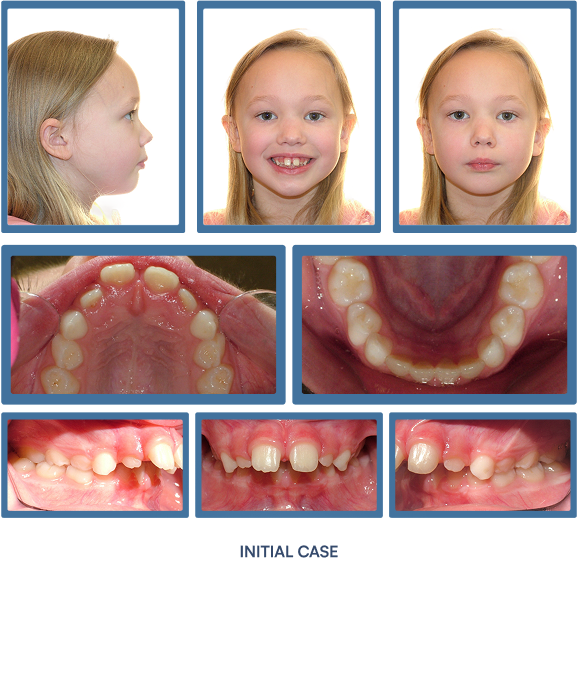

Orthodontic treatment does more than align teeth—it strategically improves the structural support of the lips and lower face. As teeth and jaws are brought into optimal alignment with braces or Invisalign®, many patients experience visibly fuller, more defined lips and an enhanced facial profile. These subtle yet impactful changes contribute to a more youthful, harmonious appearance—making orthodontics a powerful tool not only for oral health, but for facial aesthetics.